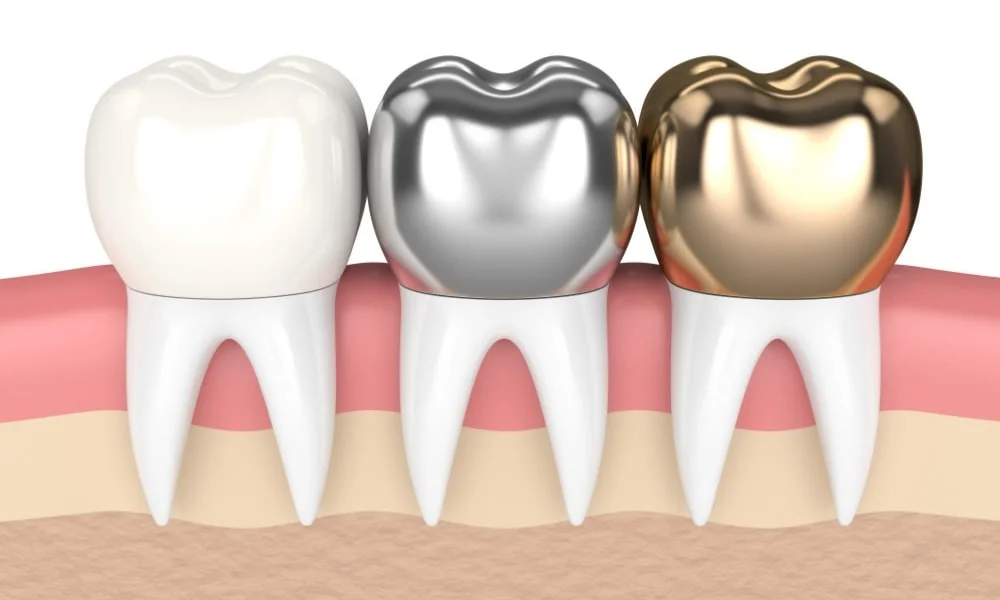

Bọc răng sứ là phương pháp thẩm mỹ dùng răng sứ làm từ chất liệu sứ hoặc kết hợp với các loại kim loại để chụp lên trên phần răng bị khiếm khuyết hay đang bị hư tổn, nhờ đó mà mang đến hình dáng và màu sắc tự nhiên cho răng.

Bọc răng sứ được xem là phương pháp nha khoa thẩm mỹ và phục hình răng tiên tiến nhất hiện nay. Mão răng hay mão sứ được tạo ra sẽ có màu sắc và hình dạng giống với răng thật, giúp tổng thể hàm răng đều đẹp tự nhiên và thẩm mỹ hơn. Các mão sứ được chế tạo trong phòng thí nghiệm (phòng Lab) và có thể được làm từ nhiều vật liệu khác nhau.

Dựa vào chất liệu sản xuất, răng sứ được phân chia thành 4 loại là răng sứ kim loại, răng sứ Titan, Răng sứ kim loại quý và răng sứ toàn sứ. Mỗi loại đều có những ưu nhược điểm riêng với mức giá khác nhau:

Răng sứ kim loại có cấu tạo khung sườn bên trong được làm từ hợp kim có độ bền chắc cao như Niken – Coban, Niken – Crom, Titan hoặc các kim loại quý. Bên ngoài được phủ một lớp sứ giúp tăng tính thẩm mỹ cho răng.

Răng sứ titan cũng có cấu trúc tương tư như răng sứ kim loại, tuy nhiên bên trong được phủ một lớp Titan. Chất liệu titan được sử dụng rất nhiều trong y học hiện đại bởi không gây dị ứng và có thể kết hợp tốt với tổ chức xương của cơ thể. Thân răng có màu sắc hơi đục và độ bóng không được tự nhiên như răng toàn sứ. Độ bền của răng sứ Titan khá cao, khoảng từ 5 đến 10 năm trở lên.

3.3 Răng sứ kim loại quý

Răng sứ kim loại quý hiếm cũng có phần bền trong được làm từ kim loại. Nhưng chất liệu được thay thế bởi các kim loại quý hiếm như vàng, platin, palladium cùng phần sứ được phủ bên ngoài. Răng sứ kim loại quý có độ bền cao, có thể tương thích với răng và nướu sau nhiều năm sử dụng.

3.4. Răng sứ toàn sứ

Răng sứ toàn sứ hay răng sứ toàn phần được chế tác từ sứ 100%, mang lại độ bền đẹp và màu sắc như răng thật. Vật liệu sứ nguyên chất có độ tương thích cao với cơ thể, không gây kích ứng. Một số sản phẩm răng toàn sứ ưa chuộng hiện nay gồm răng sứ Cercon, răng sứ Orodent, Răng sứ Ceramill…